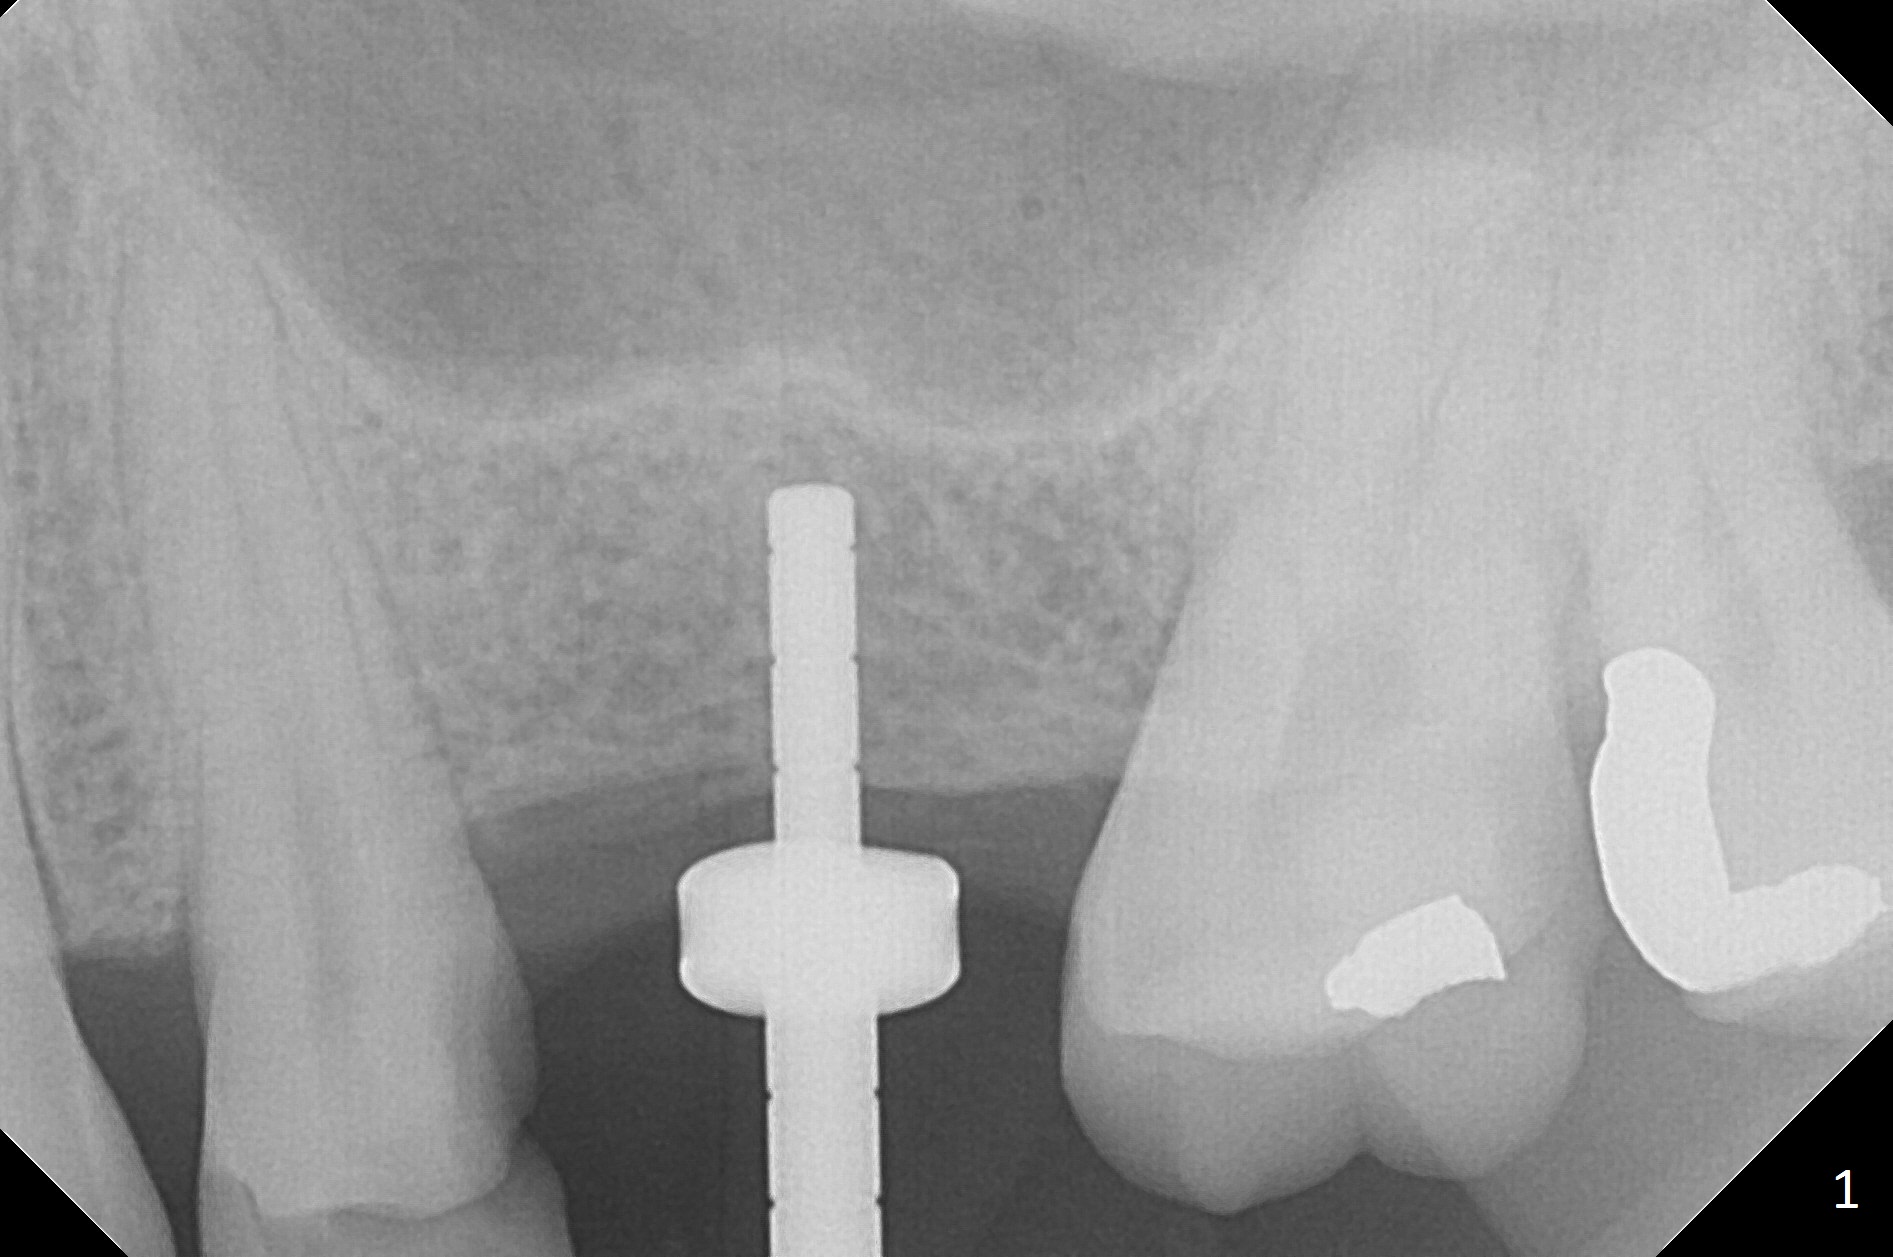

While the base of the ridge at #14 is wide, the top is moderate. IBS Magic Split is applied to gain access and test bone density (flapless). In fact the bone is hard. A 1.6 mm pilot drill is used for 9 mm (gingival level), followed by insertion of a parallel pin (Fig.1). Following Magic Expander 3.0 mm and Magic Drill 3.8 mm for ~ 11 mm (with empty feeling without air leak), a 4x11 mm dummy implant is placed with 25 Ncm (Fig.2). After insertion of a 4.5x11 mm dummy implant at 9 mm (35 Ncm; for further bone expansion), one piece of PRF plug and 1 piece of PRF membrane are pushed into the osteotomy, followed by allograft mixed with autogenous bone for sinus lift and placement of a 5x9 mm implant (Fig.3,4 with insertion torque >50 Ncm). A 6x4(2) mm abutment is placed for fabrication of an immediate provisional (Fig.5 P). There is no nasal hemorrhage postop. PRF membrane and plug are used to prevent and repair sinus membrane perforation and facilitate wound healing. There is mild bone resorption at the crest 11 months postop (Fig.6,7). The bone resorption seems to be worse 8 months post cementation (Fig.8,9); in fact the abutment screw is loose.